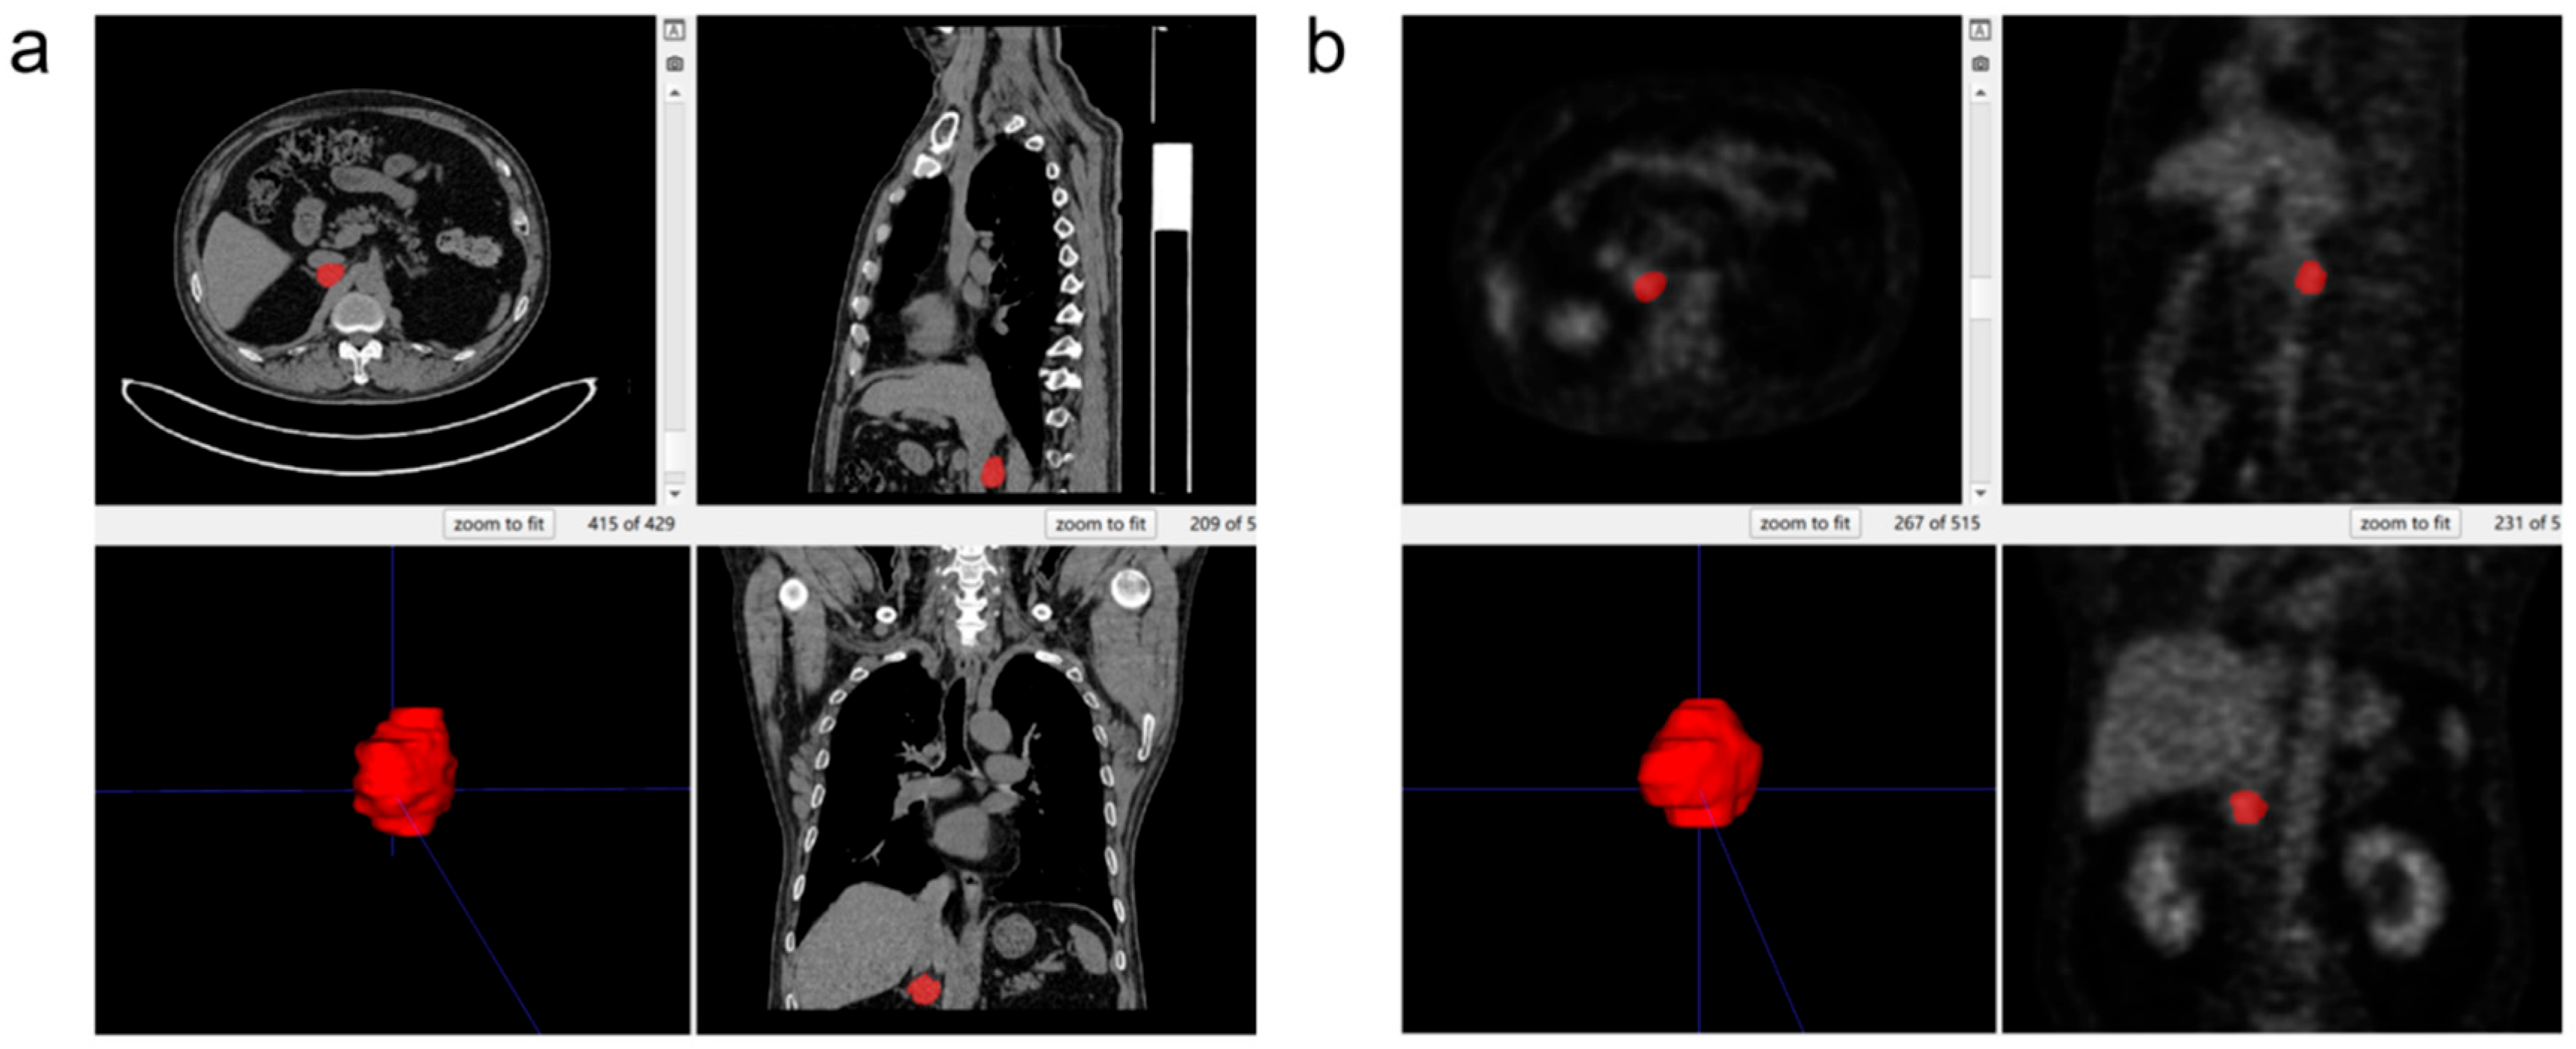

2.5. Three-Dimensional Segmentation